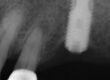

Preop radiograph from the general dentist. We do not have the exact date for this image, but I believe it was taken prior to any recovery attempts. Note the fragment position is above the first implant thread, as viewed in the right cropped image. Green arrow is the top of the implant threading, the yellow arrow is the top of the screw fragment. A Type I or II case in our fractured screw algorithm.